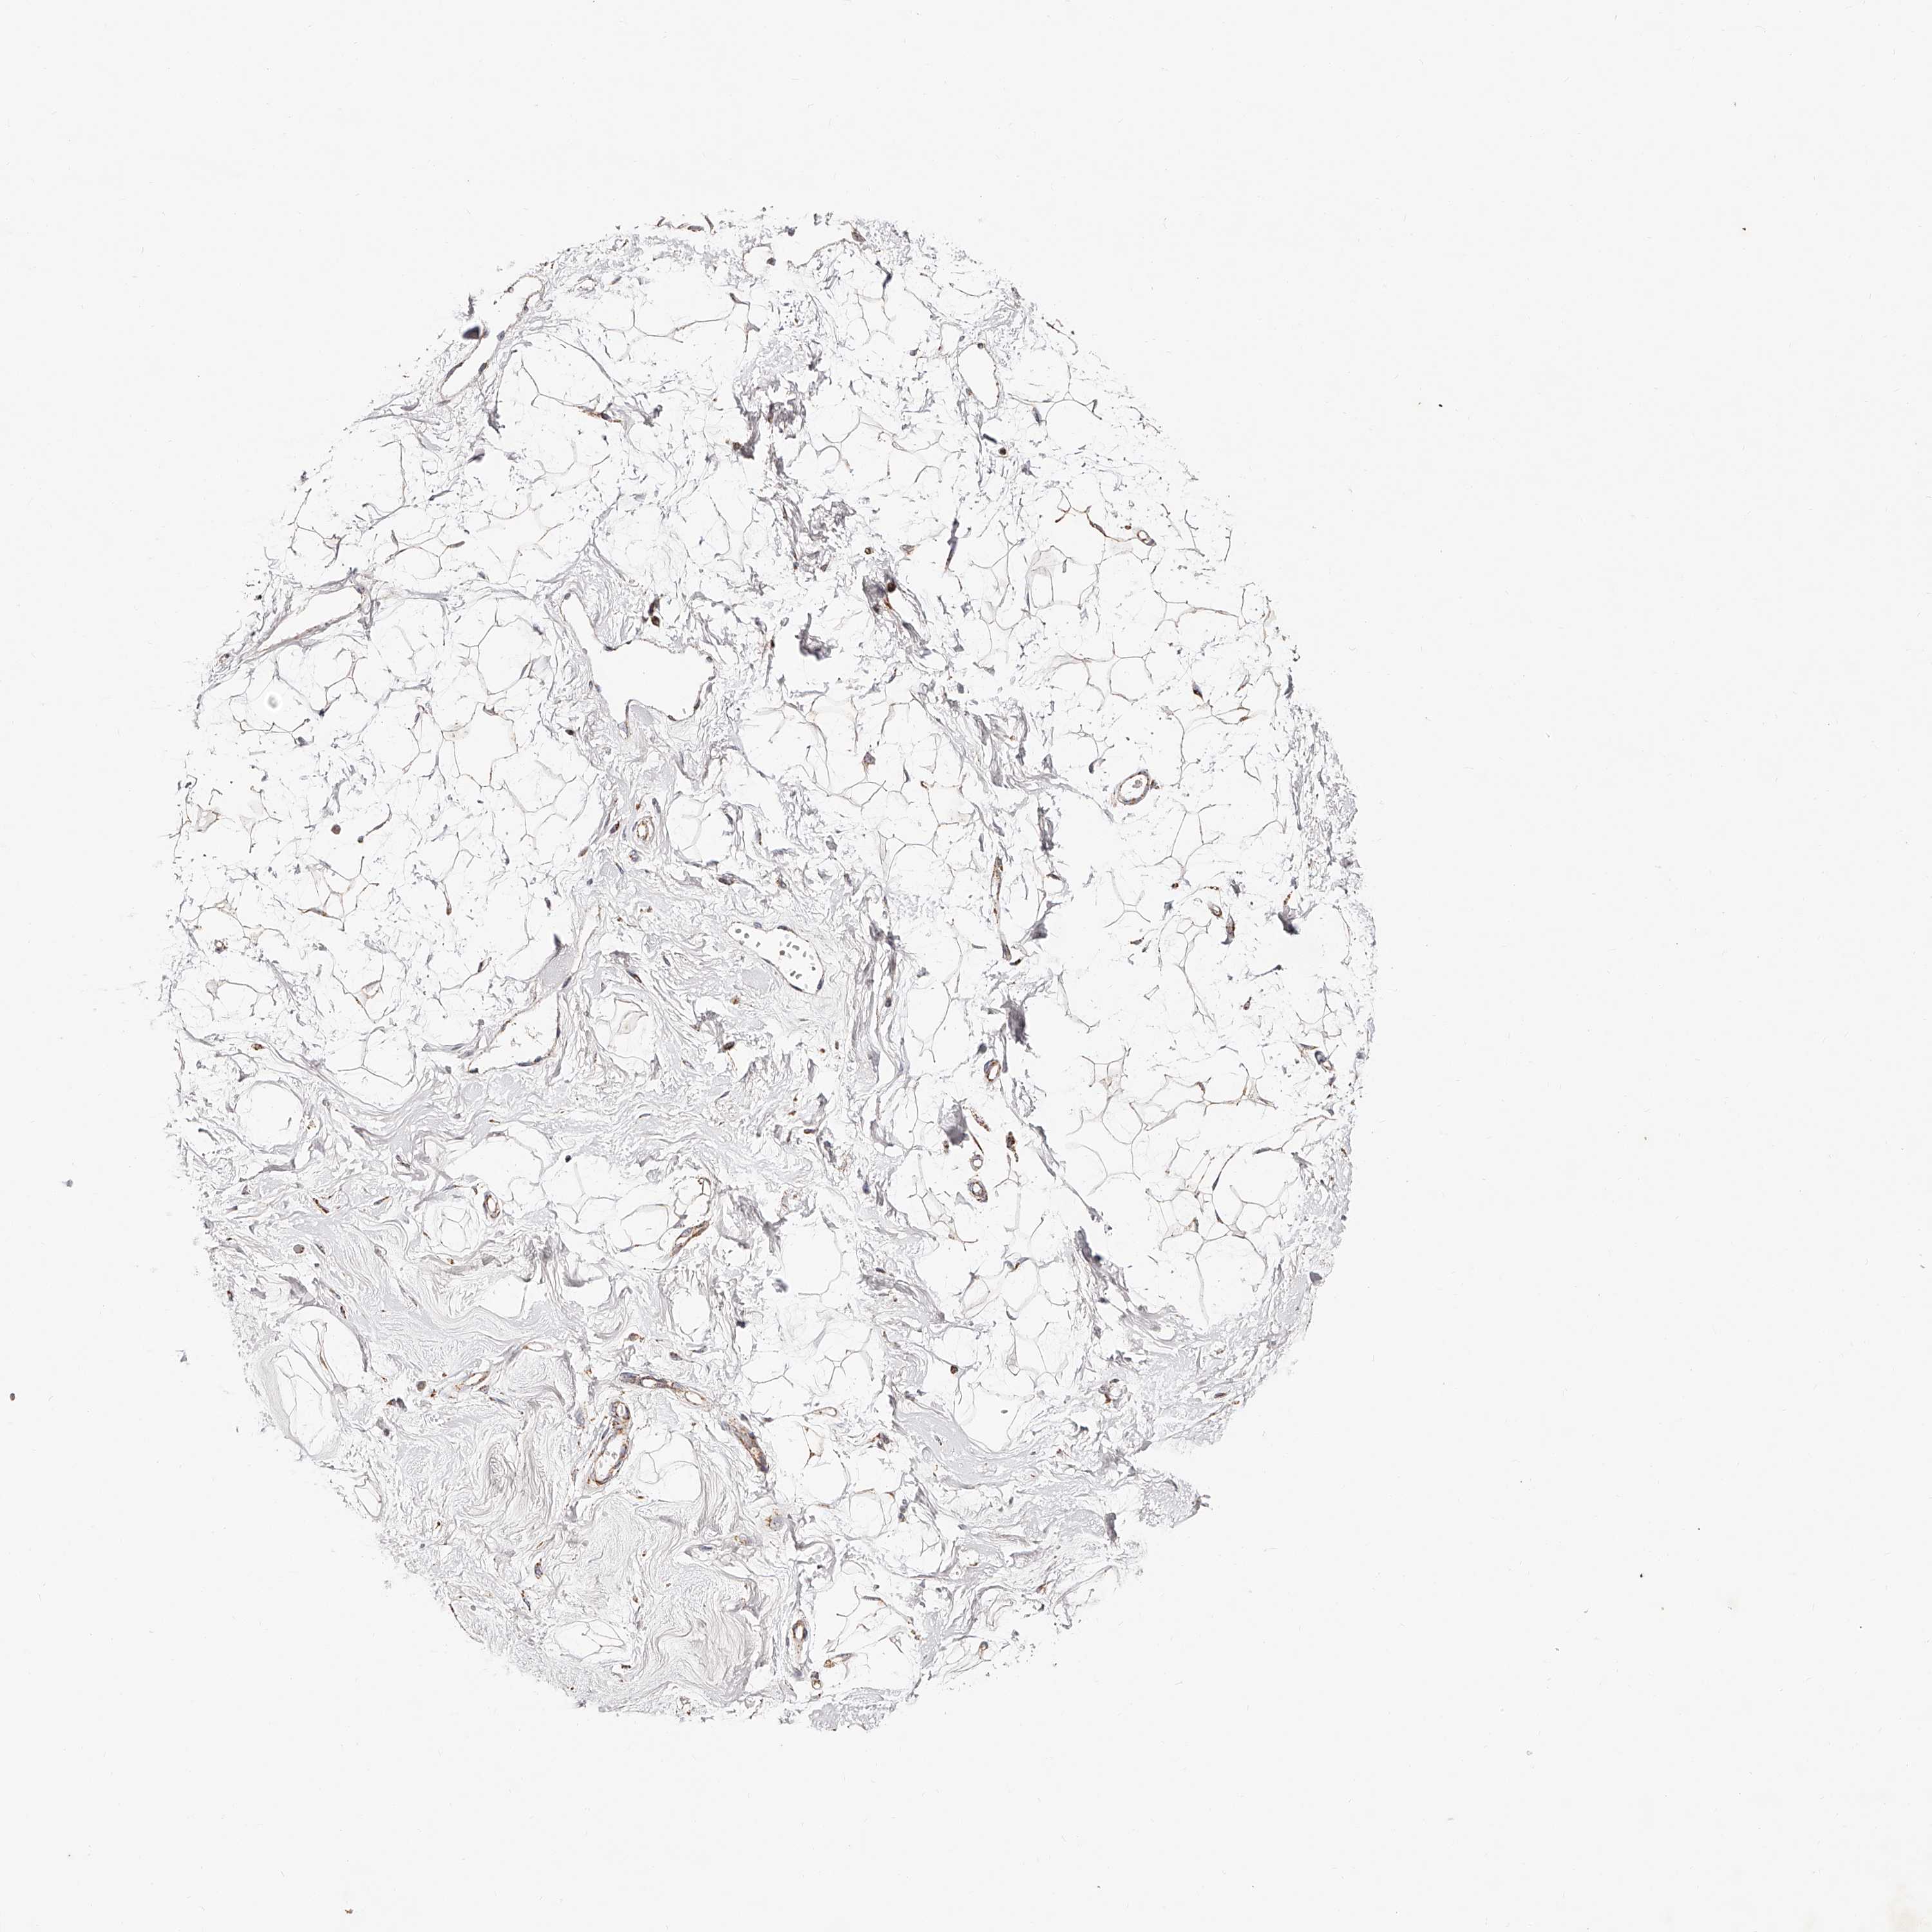

BREAST - Antibody stainingi

Antibody staining in the annotated cell types in the current human tissue is reported as not detected, low, medium, or high, based on conventional immunohistochemistry profiling in selected tissues. This score is based on the combination of the staining intensity and fraction of stained cells.

Each image is clickable and will lead to virtual microscopy that enables deeper exploration of all samples and also displays staining intensity scores, fraction scores and subcellular localization as well as patient and tissue information for each sample.

Antibody HPA019791Antibody HPA020463Antibody HPA030427Antibody CAB034142

Adipocytes MediumMediumLowLow

Glandular cells HighHighMediumHigh

Myoepithelial cells HighHighMediumHigh